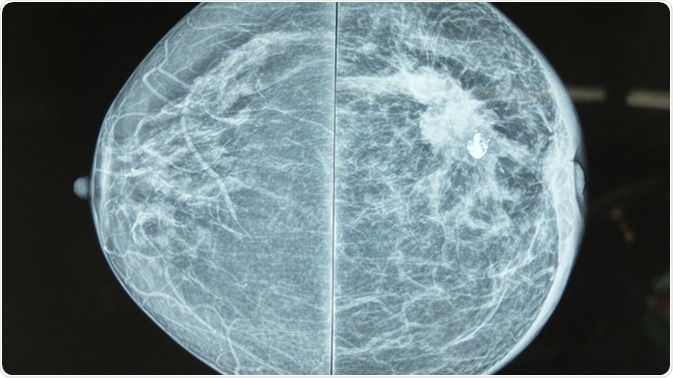

Mammography image showing left breast calcification to suggest malignancy. Image Credit: Casa Nayafana / Shutterstock

Mammography is a radiographic method which uses low-dose X-rays to image the breast tissue for both screening and diagnosis of breast cancer. Any suspicious high density regions or unusual patterns such as microcalcifications are examined carefully. These could be due to a range of abnormalities, such as tumors (benign and malignant), fibroadenomas, or cysts with solid areas.

A good mammogram requires firm breast compression against the detector. This minimizes breast movement and allows for the clearest image, it also provides the shortest distance between the breast and detector at all points, reducing the number of films and radiation exposure, while allowing single-plane imaging of the whole breast.